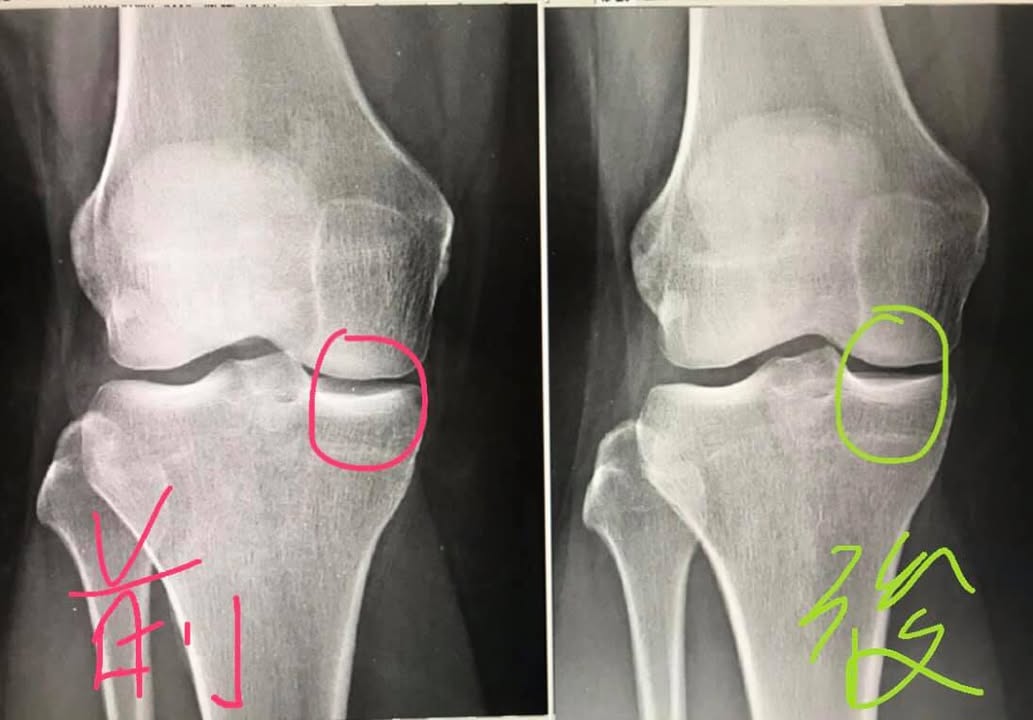

🆘蘇小姐抱怨年右膝疼痛超過四個月,之前重訓發現無法負荷重物蹲舉,在107年9月25日拍片檢查診斷退化性膝關節炎(照片左),膝關節內側間隙明顯變窄,症狀如下:走久會痠痛,平常膝關節內側明顯刺痛,下樓梯動作特別不舒服,經過健身教練介紹特地來接受膝關節針刀整合治療

蘇小姐在第三次的治療就感覺膝蓋輕鬆不少,而在八周的治療後,也就是107年11月拍片檢查,右側膝關節間隙還沒打開,又隔了一段時間,到了108/1/25,又做了四次治療後,這次很明顯發現膝關節間隙打開(照片右)。

#前後X光對比間隙打開